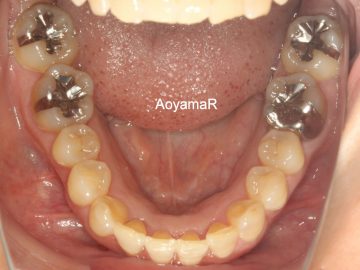

過蓋咬合(かみ合わせが深い、オーバーバイト)の矯正症例

CASE 13

(40歳 女性 )

マウスピース型カスタムメイド矯正装置(インビザライン)単独による治療

治療前

治療後